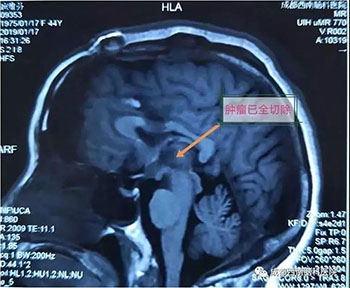

颅眶沟通性肿瘤切除手术

术前

术后(肿瘤全切)